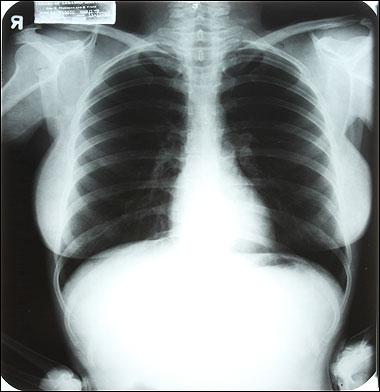

Ο υπεύθυνος των δημοπρασιών Darren Julien, εξηγεί σε συνέντευξη του τον λόγο, που τα προσωπικά αντικείμενα της Monroe είναι τόσο σημαντικά. Λέγοντας: ‘’Η Monroe έκανε πολλές ακτινογραφίες για να δει εάν είναι ή αν μπορεί να μείνει έγκυος εξαιτίας των δύο αποβολών που είχε στο παρελθόν’’.